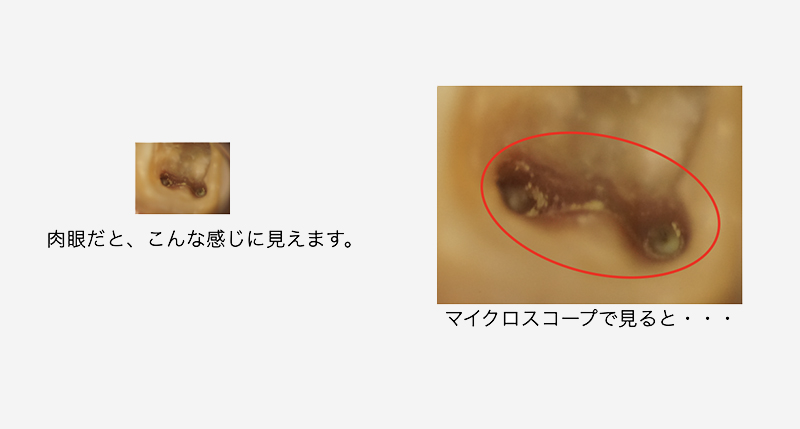

マイクロスコープ(顕微鏡)の使用

なんとなく、感覚的な治療から、確実に「見て」治療をすることが可能です。見えるからこそ、感染物(汚れ)が取れているかどうかを判断できるのです。

ラバーダムの重要性マイクロスコープで見ると

根管の内部は汚れているのがわかります。肉眼ではこの汚れは見えません。